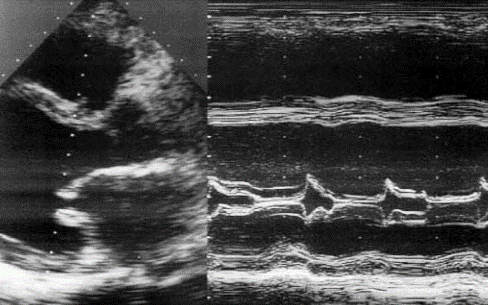

М-режим эхокардиографии является полезным в документировании асимметричного утолщения межжелудочковой перегородки, передне-систолического движения передней створки митрального клапана, и среднесистолического прикрытия аортального клапана. Непропорциональная септальное утолщение миокарда проявляется также в ПЖ и нижней стенки миокарда. Передне-систолический ход створок митрального клапана можно увидеть и в прочих гипердинамических кардиальных условиях. Двумерная (2D) эхокардиография остается главным подходом выбора для установления диагноза гипертрофическая кардиомиопатия. Кроме того, подробная морфологическая характеристика обеспечивается 2D эхокардиографической визуализацией. Наиболее частой из морфологического разнообразия выявляется гипертрофическая кардиомиопатия, которая состоит из диффузного утолщения желудочков, перегородки и переднебоковой свободной стенки (70%-75% случаев). Гипертрофия, которая сопровождается утолщением базальной зоны межжелудочковой перегородки (10%-15% случаев), концентрическая гипертрофия (5% случаев), апикальная гипертрофия (

M-режим и 2-D эхокардиография показывает:

- Расширение всех камер сердца (левого и правого желудочков и предсердий) - увеличение конечного систолического и конечно диастолического размера и объема ЛЖ

- Уменьшение толщины стенки и ее подвижности (от легкого до тяжелого) - снижение фракции выброса и частичного укорочения, уменьшение подвижности межжелудочковой перегородки и верхушки ЛЖ